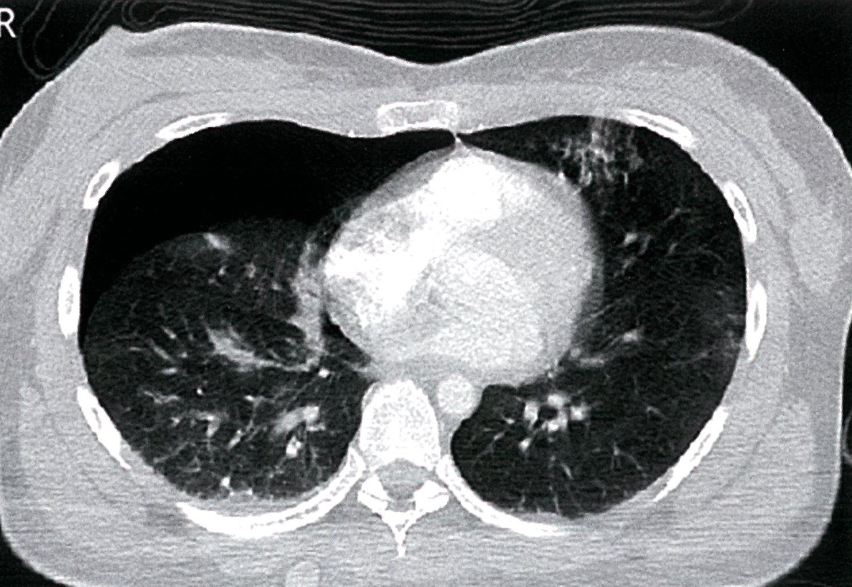

- CT thorax (axial view; lung window)

Y